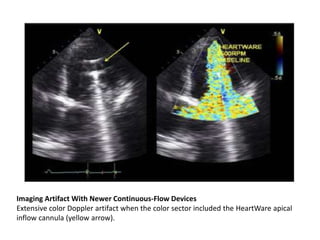

Imaging Artifact With Newer Continuous-Flow Devices

Extensive color Doppler artifact when the color sector included the HeartWare apical

inflow cannula (yellow arrow).

Imaging artifacts • Theinflow cannula produces a characteristic downfield signal LVAD, an impeller mechanism intrinsic to the inlet cannula, and the DuraHeart and HeartWare centrifugal pump housings that come in contact with inflow cannula. • When the inflow cannula is within the imaging sector, Doppler signals are severely degraded, presumably due to the production of ultrasound frequencies from the device.

Imaging Artifact WithNewer Continuous-Flow Devices Extensive color Doppler artifact when the color sector included the HeartWare apical inflow cannula (yellow arrow).